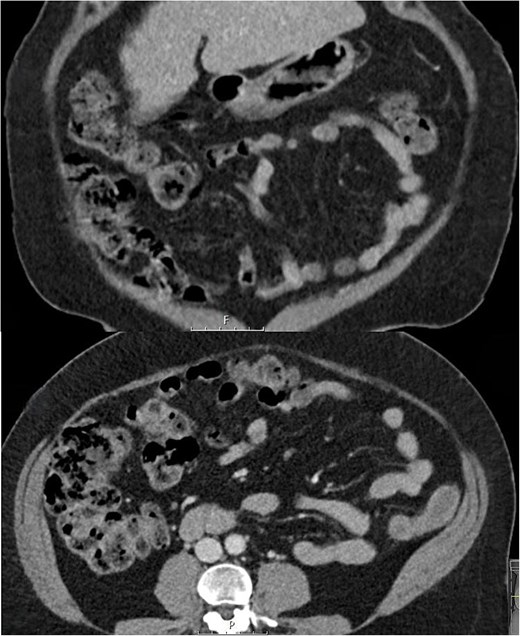

Initial treatment involved serial abdominal examination to monitor progress, stopping the lactulose, and commencing IV cefuroxime 1.5 g 8-hourly and metronidazole 500 mg 12-hourly to suppress bacterial translocation. On repeat review the patient did not deteriorate. Her symptoms of abdominal pain, bloating, and flatus, and her clinical signs of peritonism were all improving within 24 h. There was ongoing clinical improvement and a repeat CT abdomen and pelvis at 48 h showed a reduction in colonic pneumatosis and pneumoperitoneum. She was discharged on a 2-week course of oral metronidazole 400 mg twice daily. Macrogol 3350 (molaxole) sachets once daily were used for treatment of her constipation instead of lactulose and the use of probiotics to maintain a healthy gut microbiome was advised. Over the subsequent 2 weeks her abdominal pain, bloating, and excessive flatulence completely resolved—for the first time in over 2 years. An interval CT scan at 6 weeks showed no evidence of pneumatosis or pneumoperitoneum (Fig. 2). At surgical outpatient clinic follow up at 3 months she remained symptom free and was grateful to no longer be troubled by her previously persistent abdominal symptoms.

Follow up coronal and axial CT slices at 6 weeks showing resolution of PC.